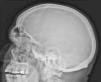

Radiographs of hands and feet (Figs. 3 and 4) showed an increase of soft tissue and joint space. In addition, the patient underwent laboratory analyses. We found serum growth hormone (GH) and IGF-1 were elevated: 5.67g/l (0–3.5g/l) and 121nmol/l (6.1–24, 8nmol/l), respectively. The patient was diagnosed with acromegaly. To complete the study she underwent a skull X-ray (Fig. 5) which featured an enlarged sella and a brain MRI detected the presence of a pituitary adenoma (Fig. 6).

Acromegaly usually is caused by a pituitary adenoma. Its prevalence is 4 cases/million. Excess GH acts on osteocytes, chondrocytes and fibroblasts, stimulating the progressive growth of acral parts of the body which results with radiological changes. Joint involvement in acromegaly is one of the most common clinical complications and may be the earliest manifestation in a significant proportion of patients. Musculoskeletal manifestations that occur in acromegaly are nonspecific, progressive and have an insidious onset, such as back pain, joint pain on the extremities, compression neuropathy and Raynaud's phenomenon.1,2

Radiologically, at an early stage, there is increased joint space due to hyaline cartilage hypertrophy that later evolves to a pattern indistinguishable from primary osteoarthritis.3